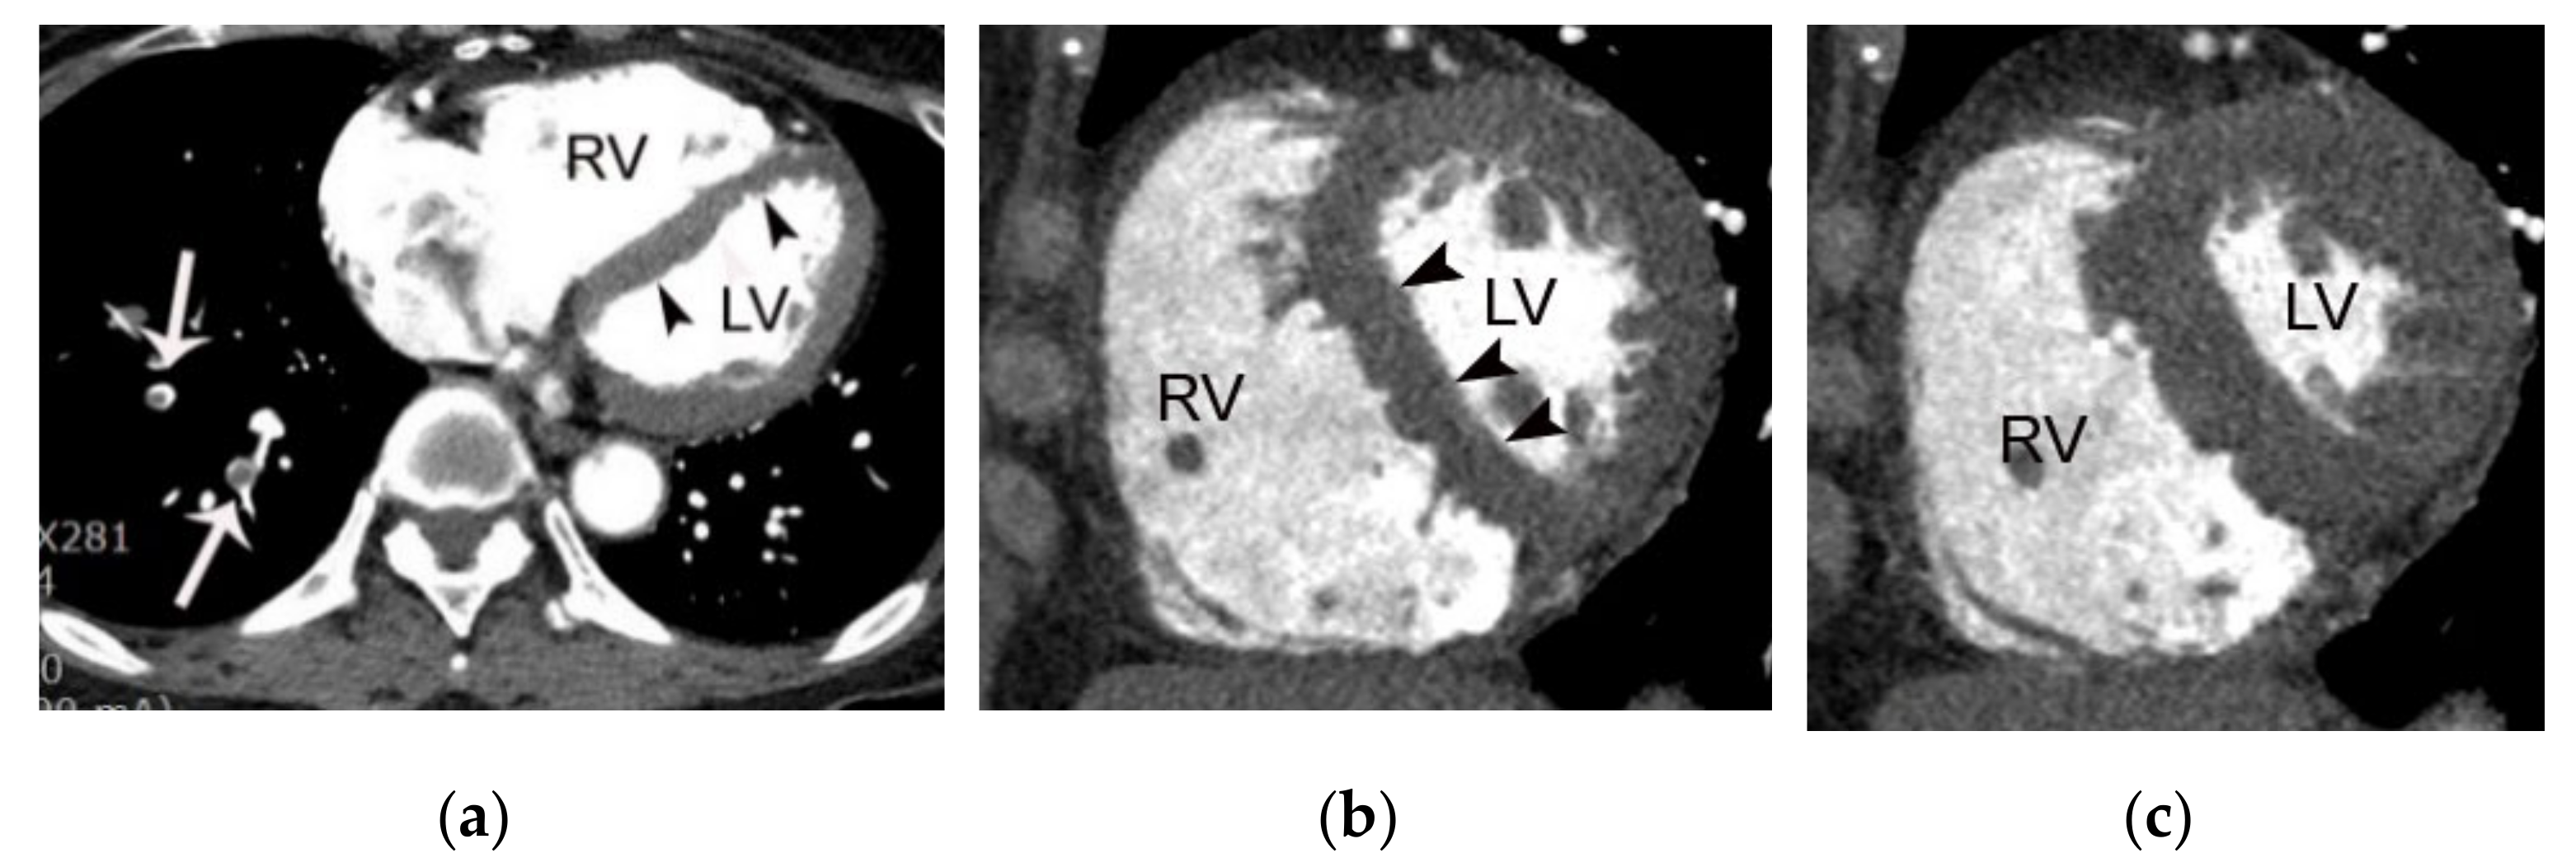

4.5. Complications of Acute Myocardial Infarction

- Moore, A.; Goerne, H.; Rajiah, P.; Tanabe, Y.; Saboo, S.; Abbara, S. Acute Myocardial Infarct. Radiol. Clin. N. Am. 2019, 57, 45–55. [Google Scholar] [CrossRef]

- Kalra, P.R.; Ohri, S.K.; Morgan, J.M. Images in cardiology. Mitral regurgitation secondary to ruptured papillary muscle. Heart 2000, 84, 13. [Google Scholar] [CrossRef] [PubMed][Green Version]

- Figueras, J.; Cortadellas, J.; Soler-Soler, J. Left ventricular free wall rupture: Clinical presentation and management. Heart 2000, 83, 499–504. [Google Scholar] [CrossRef] [PubMed]

- Higashigaito, K.; Hinzpeter, R.; Baumueller, S.; Benz, D.; Manka, R.; Keller, D.I.; Alkadhi, H.; Morsbach, F. Chest pain CT in the emergency department: Watch out for the myocardium. Eur. J. Radiol. Open 2018, 5, 202–208. [Google Scholar] [CrossRef]